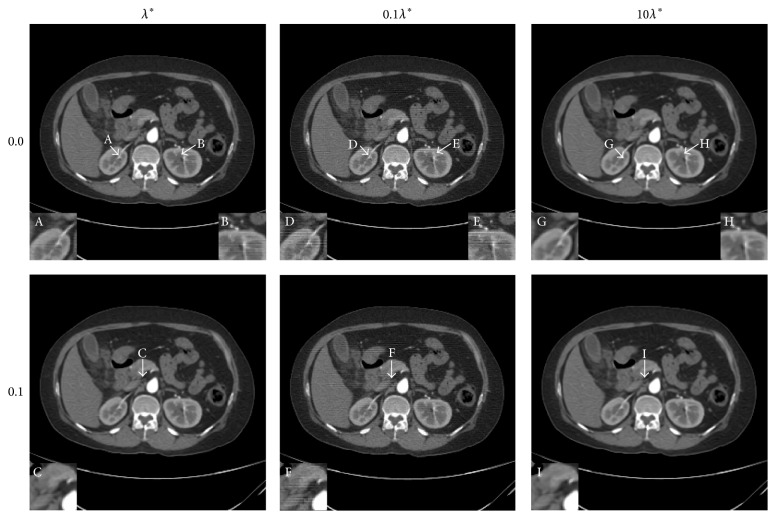

To compare the difference between different selections of the regularization parameter, the human abdomen slice image is tested as an example. The projection data are simulated by 180 views of 2° step length over a 360° range, and 512 detector elements are distributed in fan-beam geometry covering the phantom. The noise levels added to the projection data are 0.0% and 0.1% Gaussian random noise. The results are displayed in Figures 2 and 3. For the reason that biomedical images are often observed by a proper window to find more details, the images are displayed with a window [−160,400] HU. The difference between the reconstructed image and the phantom image is displayed by a window [−90,90] HU.

The results of human abdomen slice simulation study. From top to bottom, the noise levels are 0.0% and 0.1% in turn. From left to right, the regularization parameters are λ ∗, 0.1λ ∗, and 10λ ∗. The display window is [−160,400] HU.

The difference between the reconstructed image and the original image (OI) of the human abdomen slice image. From top to bottom, the noise levels are 0.0% and 0.1% in turn. From left to right, the regularization parameters are λ ∗, 0.1λ ∗, and 10λ ∗. The display window is [−90,90] HU.

The values of the two criterions are presented in Table 1. Comparing the results with the same noise level of the λ situation and the 10λ situation, the NMAD of the λ situation is smaller and the SNR of the λ situation is larger mostly, which proves that the image reconstructed by choosing the regularization parameter as λ is more close to the sample image. When it comes to the 0.1λ situation, although the values of the two criterions are a little better, there are some artifacts appearing in the reconstructed image, leading to a decline of the image quality. In the middle column of Figures 2 and 3, some horizontal line artifacts appear in the images (regions D, E, and F in Figure 2 and the ellipse regions in Figure 3). It seems that there are more horizontal artifacts in the 0.0% noise level image. The probable reason is the noise added to the projection data since the noise covers the inconspicuous artifact in the 0.1% noise level image. So what is the reason for the fact that the NMAD and SNR of the 0.1λ situation are better? One reasonable explanation might be the smoothing effect of the dictionary learning algorithm. When the iterative image is updated by (6) or (23), the sparse constraint added by dictionary learning method smoothes not only the noise but also the margin details. This effect becomes more significant when the regularization parameter is becoming larger. Therefore, the difference between the reconstructed image and the sample image in the margin area becomes more obvious, which is displayed in the left and right columns of Figure 3. By discovering this effect making the criterion worse, future work should be devoted to improving the reconstruction algorithm based on dictionary learning in order to smooth the noise and preserve the margin details meanwhile.